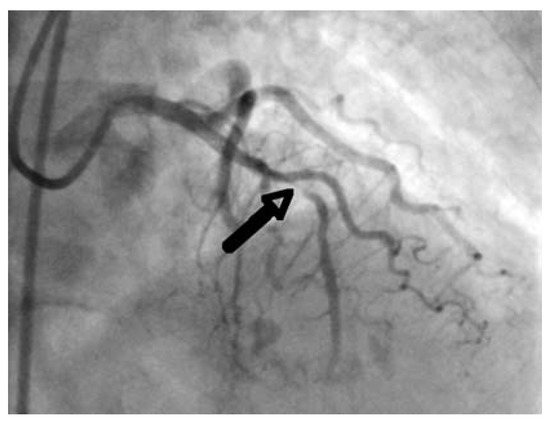

Mechanism of Sudden Cardiac Death in Coronary Artery Disease

Case report